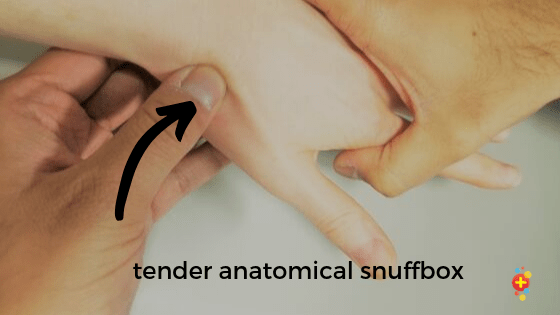

(1) 코담배갑부위 압통(Snuffbox tenderness)

-

- 코담배갑부위를 눌렀을 때 압통여부를 확인합니다.